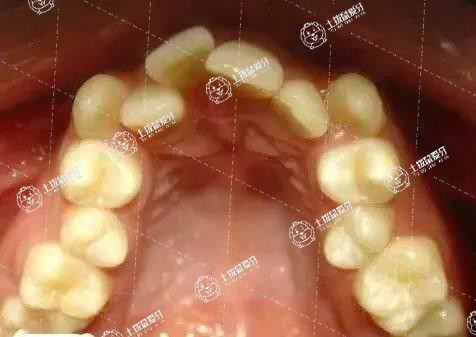

牙列擁擠輕度者可以直接帶上牙套進行排齊,如果擁擠嚴重,可能需要拔牙治療,如果擁擠程度較輕,簡單的排齊會有輕微的突出,就需要對前牙的鄰面進行去釉處理,就是前牙稍微磨掉一點排齊。如果不想磨牙,又沒有智齒或智齒要拔掉,把牙齒往后推,空出間隙和前牙排齊即可。

牙齒擁擠矯正通常需要一年或者兩年的時間。每個人牙齒的情況都不太一樣,所以牙齒矯正需要的時間也不一樣,具體時間還需要到專業(yè)牙科就診檢查之后才能確定。牙齒矯正的材料和方式有很多,例如功能托槽、活動托槽、固定托槽等,可以根據(jù)自己的實際情況來選擇合適的材料和治療方案。在進行牙齒矯正時,不要吃太甜的食物,避免齲齒的出現(xiàn)。

如果是輕度的牙列擁擠,這種情況不需要拔牙,可以采用固定矯正或隱形矯正的方法來進行治療,這種情況下需要的時間比較短,可能需要一年就可以了。但是如果是重度的牙列擁擠,嚴重的時候還需要拔牙,這樣才能夠進行矯正,這種情況需要的時間可能會長一些,可能需要兩年到三年。另外牙列擁擠矯正時間還和患者的年齡有關,一般兒童矯正的時間會短,但是如果是成年人,矯正的時間會長一些。